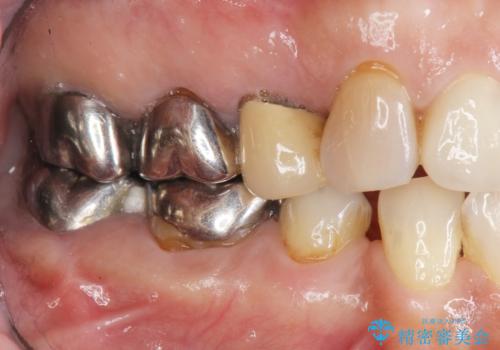

- 58.3万円(ジルコニアクラウン×4・仮歯×4・歯槽堤保存術)費用は治療当時の料金となります

ブリッジによる補綴を行うことで周囲の歯の噛み合わせも改善ししっかりと噛むことができるようになりました。